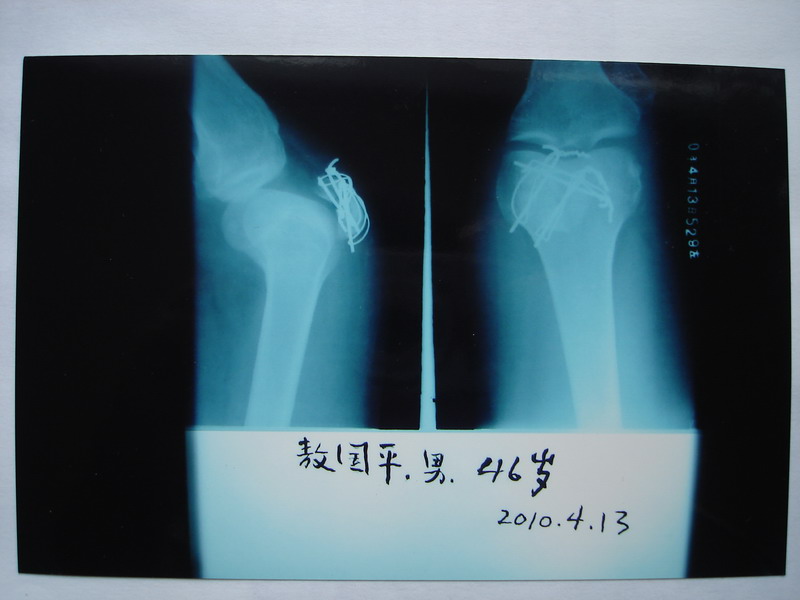

敖国平 (左髌骨骨折术后27天)